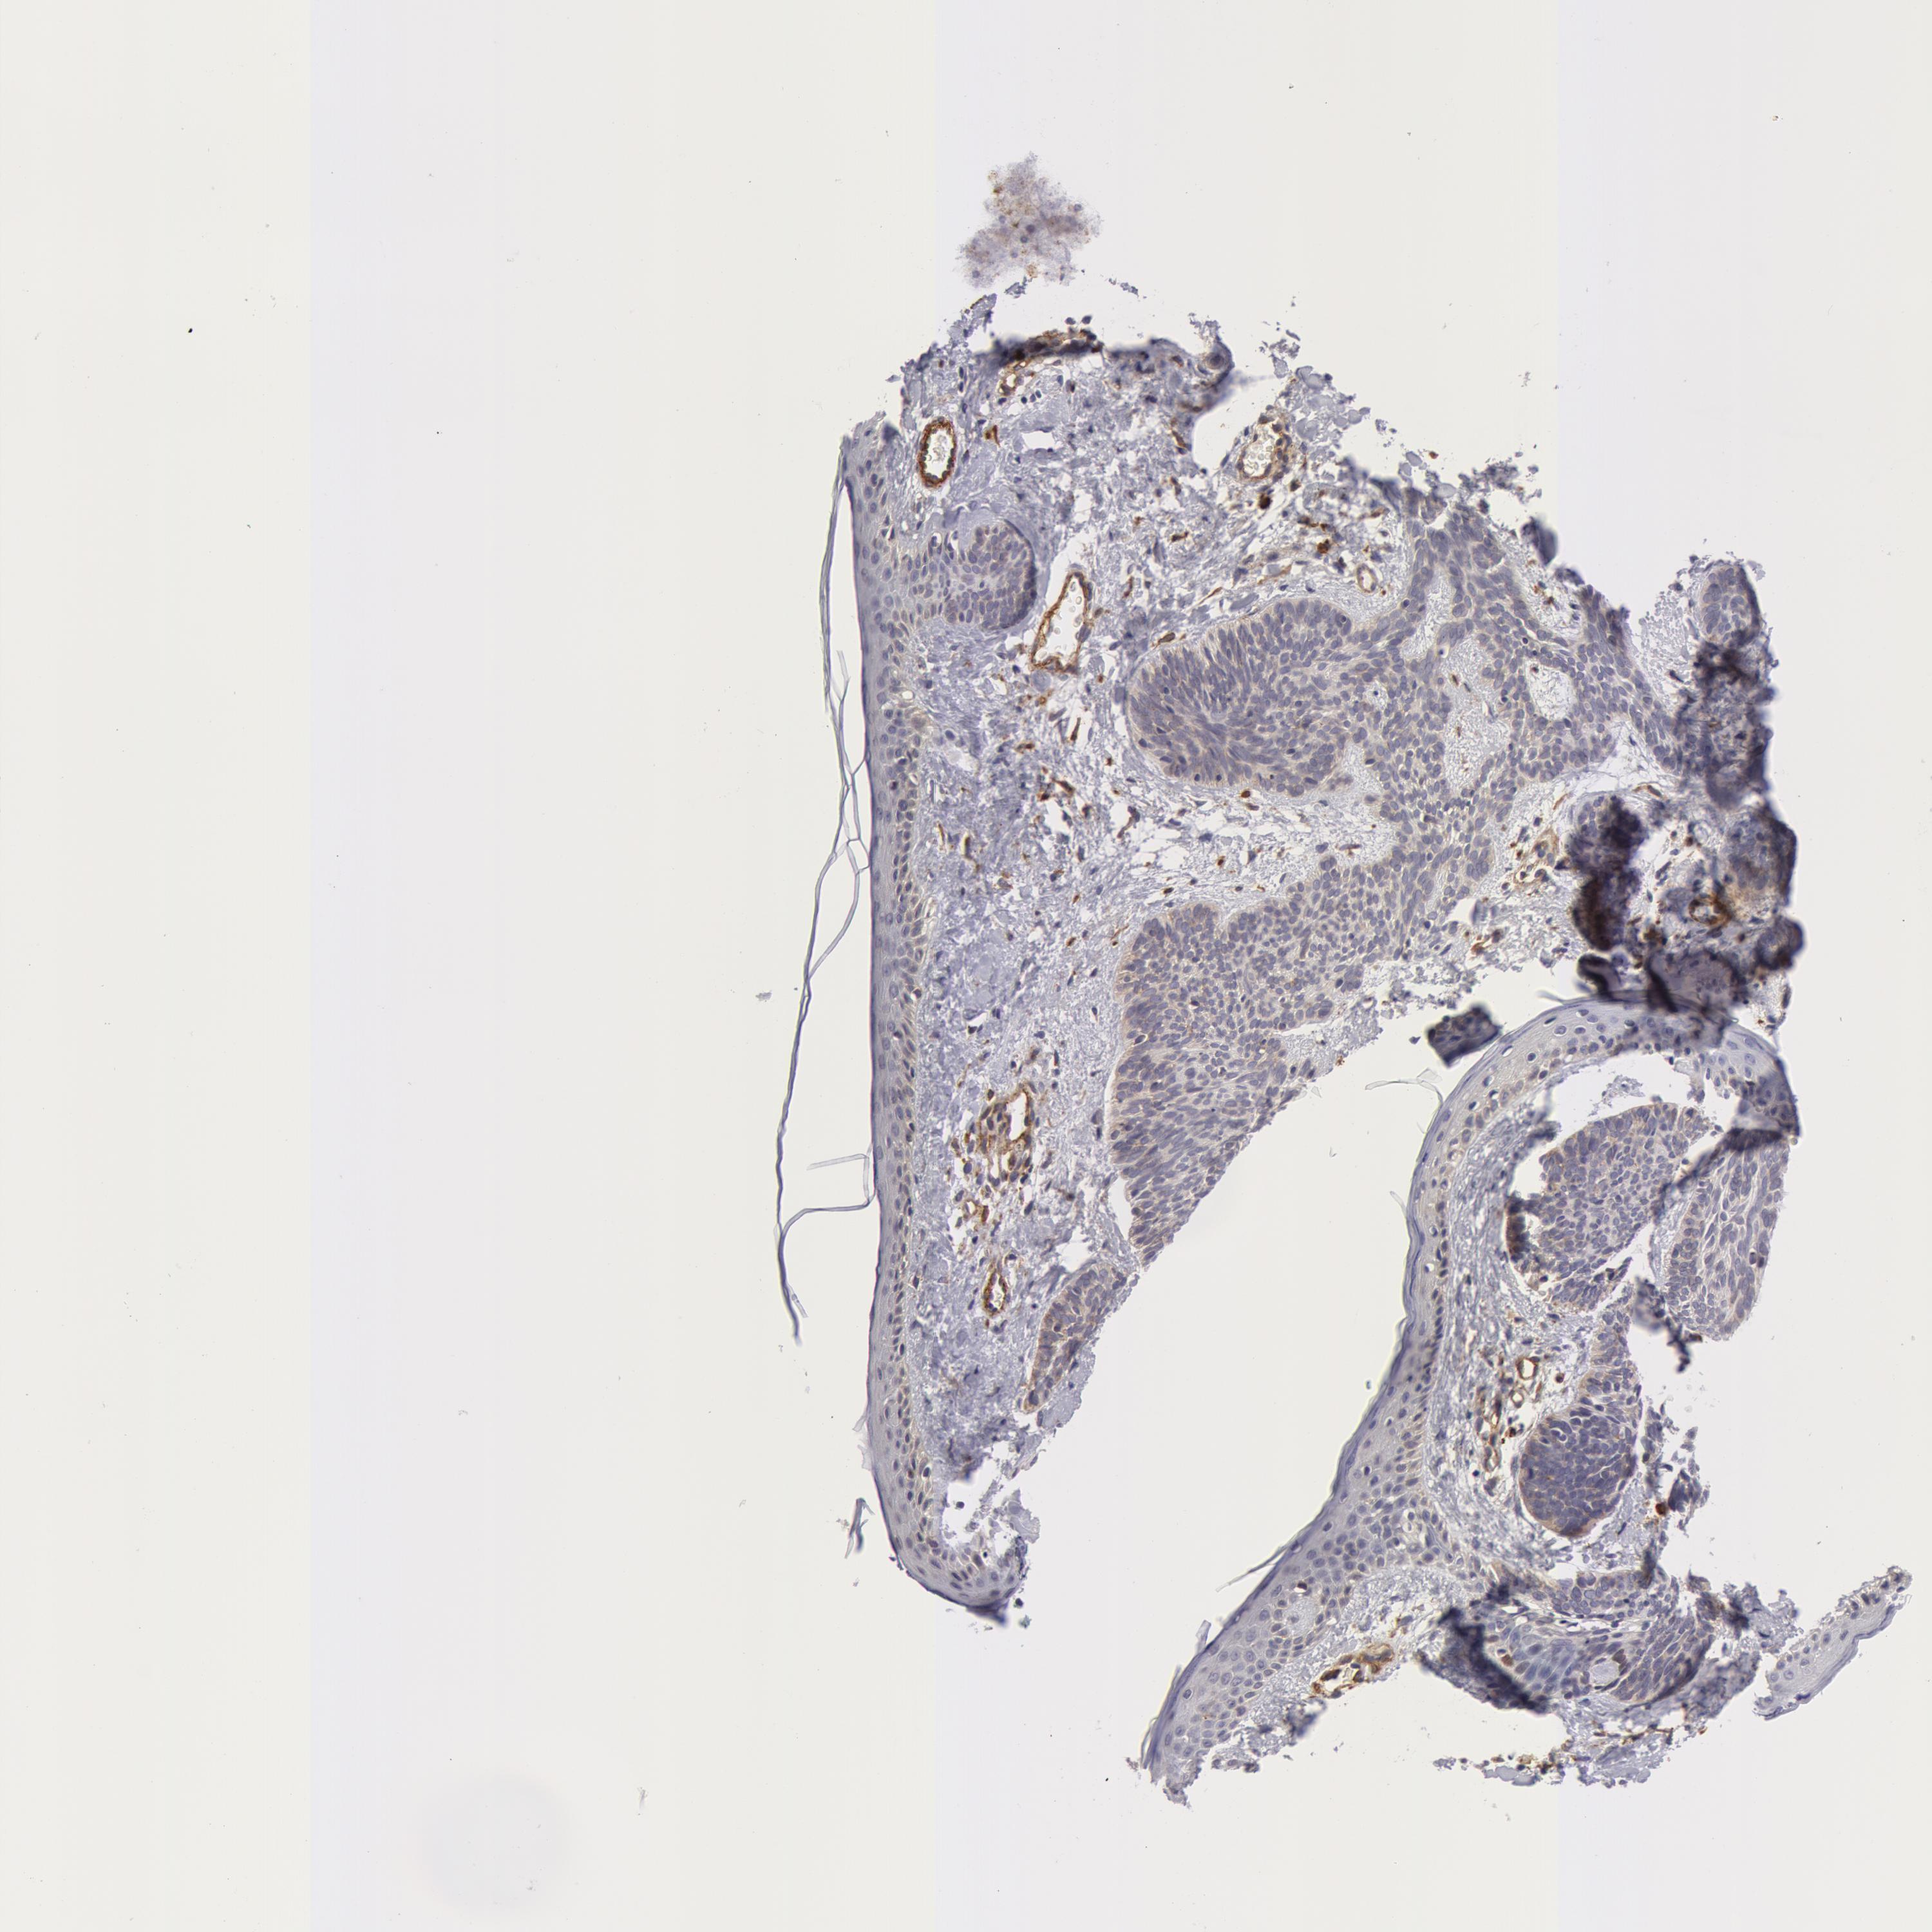

SKIN CANCER - Protein expressioni

A mouse-over function shows sample information and annotation data. Click on an image to view it in a full screen mode. Samples can be filtered based on level of antibody staining by selecting one or several of the following categories: high, medium, low and not detected. The assay and annotation is described here.

Antibody stainingi

Antibody staining in the annotated cell types in the current human tissue is reported as not detected, low, medium, or high, based on conventional immunohistochemistry profiling in selected tissues. This score is based on the combination of the staining intensity and fraction of stained cells.

Each image is clickable and will lead to virtual microscopy that enables deeper exploration of all samples and also displays staining intensity scores, fraction scores and subcellular localization as well as patient and tissue information for each sample.

Antibody HPA001554

Staining

High

Medium

Low

Not detected

Intensity

Strong

Moderate

Weak

Negative

Quantity

>75%

75%-25%

<25%

None

Location

Nuclear

Cytoplasmic/membranous

Cytoplasmic/membranous,nuclear

Squamous cell carcinoma, NOS

Basal cell carcinoma